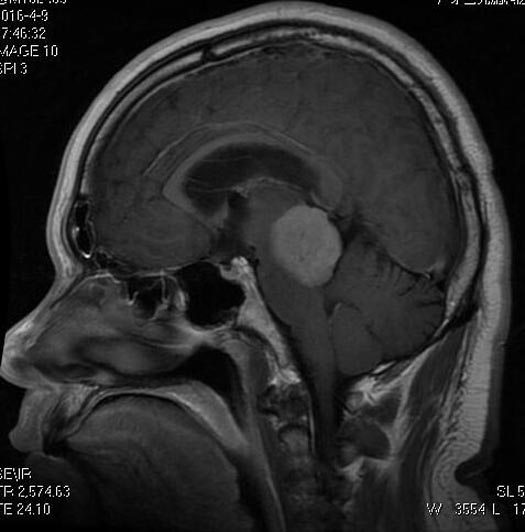

广东三九脑科医院行头颅MR检查显示:右侧小脑幕跨幕上下区示一肿块,大小约为4.0cm×3.8cm×3.6cm;邻近脑组织受压移位,以中脑尤为明显,其内中脑导水管及三脑室受压变窄,幕上脑室系统扩大,考虑脑膜瘤可能性大;头颅CTA检查提示:右侧跨小脑幕上下占位病变内血管丰富,右侧大脑后动脉受压向上移位。